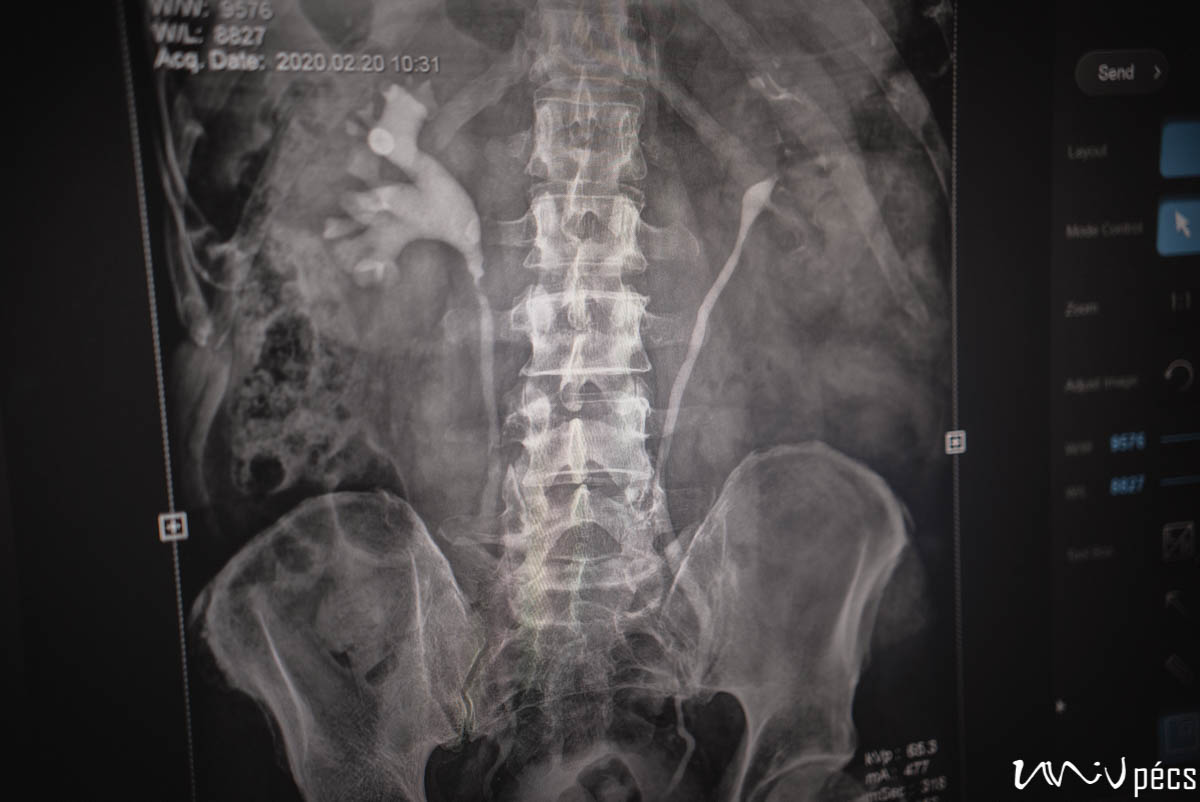

A prosztatarák a férfiak egyik leggyakoribb daganatos megbetegedése. Magyarországon évente több ezer új esetet diagnosztizálnak, de korai felismeréssel szinte mindig gyógyítható. A betegség azonban korai stádiumban sokszor nem okoz tünetet – ezért különösen fontos az évenkénti urológiai szűrés 45 év felett (vagy korábban, ha a családban előfordult ilyen betegség). A vizsgálat gyors, kíméletes és fájdalommentes: vérvétellel laborvizsgálat (ahol a PSA-szintet ellenőrzik), ultrahang és fizikális ellenőrzés.

A Pécsi Tudományegyetem Klinikai Központ Urológiai Klinikája nemcsak a Dél-Dunántúl, hanem az ország egyik legfontosabb szakmai központja.

Teljes urológiai ellátás működik, azaz a prosztata- és herebetegségek diagnosztikáját és kezelését, vesekő- és húgyúti problémákat látnak el az itt dolgozó szakorvosok, uroonkológiai műtéteket (pl. prosztata-, hólyag- és vesedaganatok) valamint lézeres és minimálisan invazív beavatkozásokat végeznek el, de rekonstrukciós és funkcionális urológiával és andrológiai ellátással (férfimeddőség, potenciazavarok kezelése) is foglalkoznak.